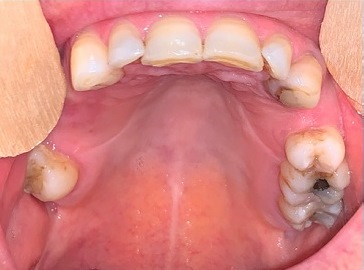

O exame físico revelou um abaulamento assimétrico do hemi‑palato duro esquerdo revelando uma lesão dura, edemaciada e restrita à região edemaciada (Figuras 1 e 2).

Figura 2 Lesão intra‑ oral localizada no hemi‑palato duro (sem prótese removível esquelética colocada)

A doente iniciou tratamento com imuno‑quimioterapia segundo o protocolo R‑CHOP (rituximab, ciclofosfamida, doxorrubicina, vincristina e prednisolona), durante 6 ciclos. No fim do 3.º R‑CHOP foi possível observar a total regressão da lesão do palato (Figuras 9 e 10). A doente completa os 6 ciclos de quimioterapia com resposta completa e prossegue tratamento com rituximab de manutenção a cada 2 meses, durante 2 anos.

Figura 10 Regressão total da lesão anteriormente observada hemi‑palato (sem prótese removível esquelética)